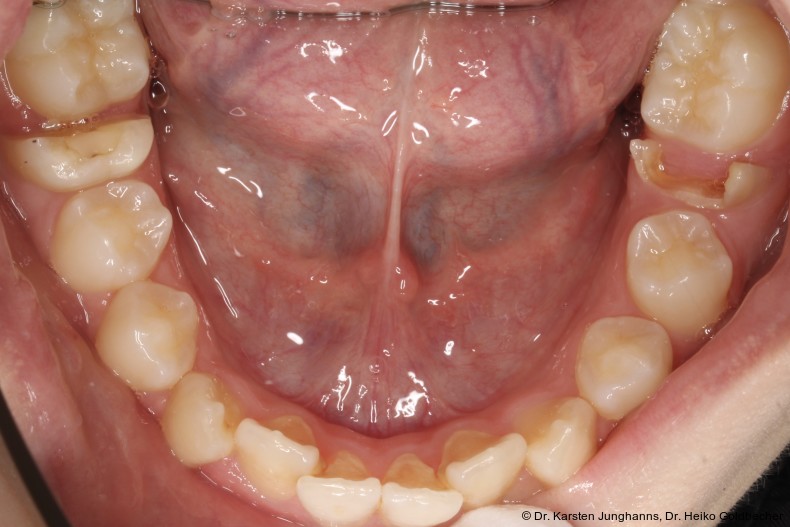

Eine Patientin stellte sich im Alter von neun Jahren erstmals vor. An den ersten Molaren des Unterkiefers wurden vom Hauzahnarzt eine MIH diagnostiziert (Abb. 1a) und die Zähne als nicht erhaltungsfähig eingestuft. Die beiden ersten Molaren wurden hemiseziert und der distale Anteil extrahiert. Gut zu erkennen ist auf dem OPG die annähernd achsengerechte Mesialisierung der zweiten Molaren sowie die Aufwanderung der Zahnkeime der dritten Molaren (Abb 1b: ca. 1,5 Jahre nach Hemisektion). Noch vor Durchbruch der zweiten Molaren in die Mundhöhle wurde auch der mesiale Anteil entfernt. Der spontane Lückenschluss erfolgte innerhalb der nächsten anderthalb Jahre (Abb. 1c). Die endgültige Achsstellung kann nach Ausdehnung der Teilmultibandapparatur eingestellt werden.

Auch wenn nach dem Minimalschadensprinzip meist der Zahnerhalt anzustreben ist, können die Begleitumstände eine Extraktion rechtfertigen. Der Hauszahnarzt übernimmt in der Regel eine Schlüsselrolle im Entscheidungsprozess und der möglichen Einbeziehung von Fachzahnärzten. Erfahrungsgemäß treten insbesondere im Unterkiefer Komplikationen in Form von Alveolenkollaps und der sich daraus entwickelnden Nebenwirkungen auf, welche es zu vermeiden oder zu verhindern gilt. Bei der Indikation zur Extraktion eines Unterkiefermolars sollte eine Hemisektion in Erwägung gezogen werden. So kann mit wenig Aufwand ein achsengerechter Spontandurchbruch der zweiten und dritten Molaren erreicht werden. Sollte die Entscheidung zu einem späteren Zeitpunkt getroffen werden, kann auch hier durch eine Mesialisationsmechanik (Abb. 2c) eine körperliche und achsengerechte Einstellung erreicht werden. Gut zu erkennen ist in Abbildung 2, dass der dezente frontale Engstand weiterhin besteht und keine Distalisierung der Frontzähne oder Prämolaren stattgefunden hat. Spätere Extraktionen mit Komplikationen können vermieden werden. Bisher hat diese Indikation zur Hemisektion (MIH) noch keinen Eingang in den Bema gefunden. In Hinblick auf ein verbessertes Lückenmanagement mit geringeren Risiken, verkürzten Behandlungszeiten, geringerem apparativen und finanziellen Aufwand sollte eine Anpassung zukünftig diskutiert werden. Falls der dritte Molar angelegt ist, wird in vielen Fällen ein Lückenschluss mit Einordnung der zweiten und dritten Molaren möglich sein, sodass am Behandlungsende ein adultes Gebiss mit 28 gesunden Zähnen vorliegt.